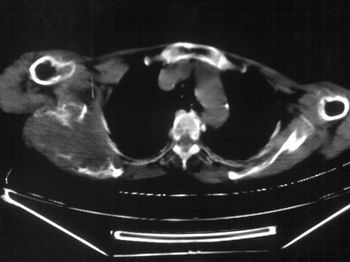

以下是引用dyqct在2007-9-11 16:52:00的发言:[br]支持右肩胛骨恶性肿瘤,性质不好定。

以下是引用zhangxu5888在2007-9-11 16:25:00的发言:[br]有侧肩胛骨溶骨性破坏且见软组织成分,增强软组织强化明显,中央见低密度坏死区!根据病史10年,考虑良性肿瘤恶性变!性质待定!

以下是引用老爱克斯新网客在2007-9-11 18:22:00的发言:[br]应该是良性肿瘤恶变,但因晚期破坏严重不能见到原来肿瘤征象无法判断,